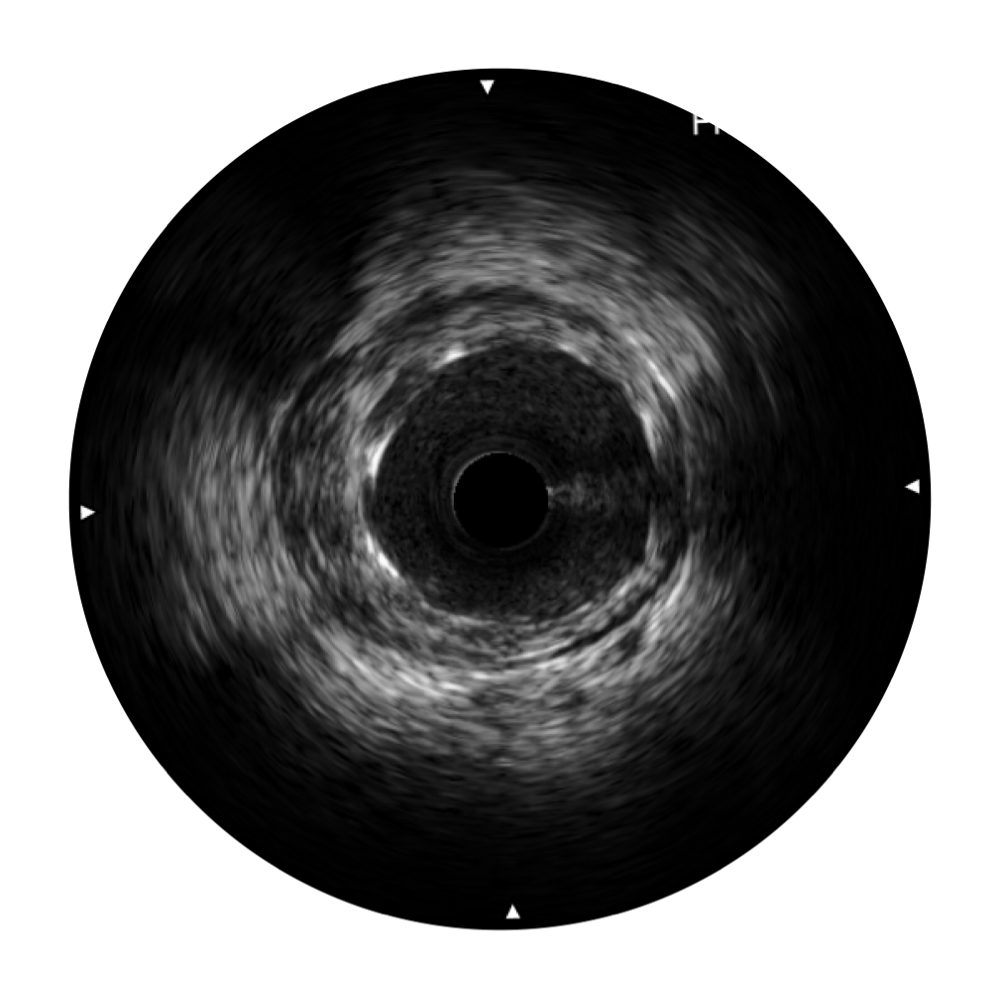

传统IVUS图像

对比传统IVUS导管成像,开立宽频IVUS图像的近场支架梁显影更细腻,远场中膜外血管仍清晰可辨,兼顾远中近,兼顾分辨力与穿透深度